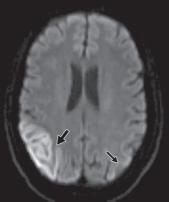

图 3A —患有线粒体脑肌病、乳酸性酸中毒和中风样发作 (MELAS) 的梗死患者的 MR 图像。T2 加权图像显示两个枕叶信号增加,右侧(粗箭头)大于左侧(细箭头)。

图 3B —患有线粒体脑肌病、乳酸性酸中毒和中风样发作 (MELAS) 的梗死患者的 MR 图像。弥散加权图像也显示双侧高信号,右侧(粗箭头)大于左侧(细箭头)。

图 3C —患有线粒体脑肌病、乳酸性酸中毒和中风样发作 (MELAS) 的梗死患者的 MR 图像。表观扩散系数图像(ADC)显示右侧信号减弱(粗箭头)但左侧信号正常(细箭头)。因此,右侧病变为急性梗死,弥散受限。左侧病变代表亚急性或慢性梗塞,弥散加权图像上有 T2 透过效应。

MRI 也可用于急性卒中,尽管技术和人员要求限制了它在许多中心的应用。DWI 是检测超急性梗塞(出现后 < 30 分钟)最敏感的序列,先于 CT(6 小时)和 T2 加权成像(6-12 小时)识别病情变化。急性梗塞中的扩散受限分别对应于 DWI 和 ADC 图上信号增加和减少的区域。随着梗死发展为亚急性和慢性阶段,会发展为血管源性水肿和脑软化症。这反映在 T2/FLAIR 信号强度的逐渐增加,且伴随着扩散系数的正常化(图3A ), 3B, 和3C)。也可以进行3D-TOF MRA或者3D-ASL检查。然而,与 CT 相比,空间分辨率较差,图像容易出现运动、磁化率和流动伪影。